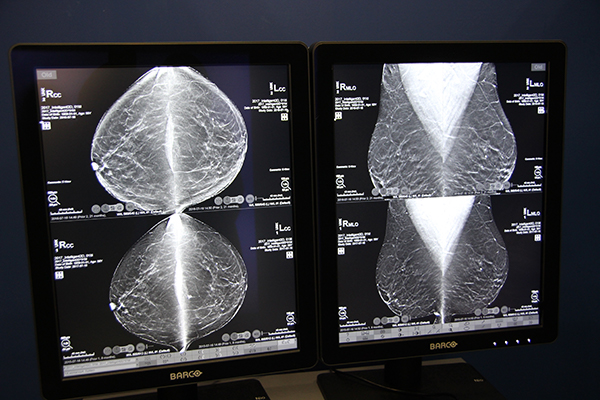

3Dimensionsは,トモシンセシス撮影機能を搭載した主力装置「Selenia Dimensions」の後継機種で,トモシンセシス画質の向上,新デザインの圧迫板「SmartCurve」の採用,操作性の向上が図られた最新システム。トモシンセシス画像再構成アルゴリズム“ClarityHD”では,鮮鋭度と粒状性の良い画像を取得でき,トモシンセシス画像から作成される合成2Dの“Intelligent 2D”もアーチファクトがなく,通常の2Dに近い画像を提供する。SmartCurveは,従来は平面である圧迫面に乳房の形に沿ったカーブをつけることで,圧迫時の痛みの軽減を図る。また,Cアームの退避や,操作ボタンをCアームにも設けるなどポジショニング時の操作性を考慮したデザインを追究した。

ClarityHDにより高画質化した合成2D Intelligent 2D